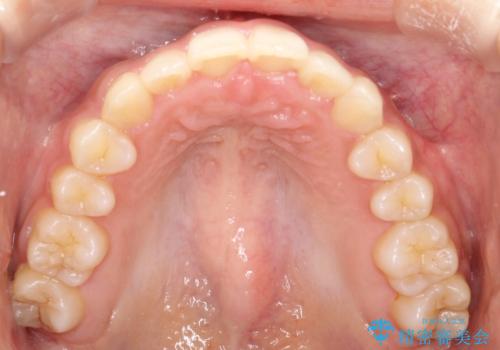

- 前歯のガタガタを主訴に来院された患者様です。

八重歯になっており、下顎の前歯が上顎の前歯に隠れてしまう、ディープバイトという状態でした。

インビザラインを使用して矯正する計画としました。

ディープバイトの場合、ワイヤー装置の装着が難しいことがあります。

インビザラインではかみ合わせに左右されず装着できるメリットがあり、ワイヤーに比べインビザラインの方が治療しやすい場合もあります。